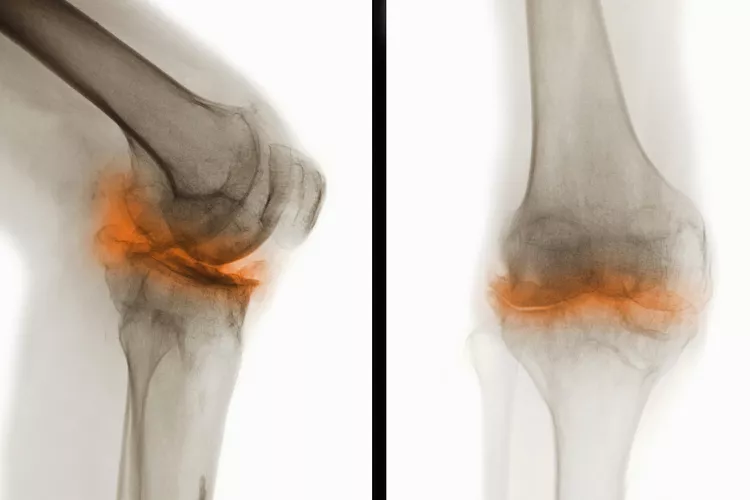

骨關(guān)節(jié)炎(Osteoarthritis, OA),一種常見(jiàn)的慢性關(guān)節(jié)疾病,主要特征是關(guān)節(jié)軟骨退化和關(guān)節(jié)邊緣骨質(zhì)增生。隨著病情進(jìn)展,骨關(guān)節(jié)炎不僅會(huì)導(dǎo)致關(guān)節(jié)疼痛和功能受限,還可能引發(fā)一系列并發(fā)癥,影響患者的整體健康和生活質(zhì)量。

在骨關(guān)節(jié)炎(OA) 中,覆蓋骨頭末端并幫助骨頭相互滑動(dòng)的光滑軟骨會(huì)逐漸磨損。這會(huì)導(dǎo)致骨頭相互摩擦和磨擦。

關(guān)節(jié)損傷

可能的問(wèn)題包括:

- 脊柱神經(jīng)受到擠壓(后天性脊椎滑脫或脊椎狹窄)

- 關(guān)節(jié)感染,但這種情況很少見(jiàn)

- 關(guān)節(jié)周?chē)募‰旌晚g帶變薄或撕裂,導(dǎo)致關(guān)節(jié)不穩(wěn)定

- 軟骨溶解癥,軟骨突然完全破裂,導(dǎo)致關(guān)節(jié)內(nèi)組織松散

- 應(yīng)力性骨折,由于反復(fù)的壓力而緩慢地在骨頭上形成細(xì)微裂縫

- 貝克囊腫是膝蓋后面的軟性充滿液體的腫塊。它們大多無(wú)痛,但會(huì)壓迫血管導(dǎo)致腿部腫脹,或破裂并引起疼痛